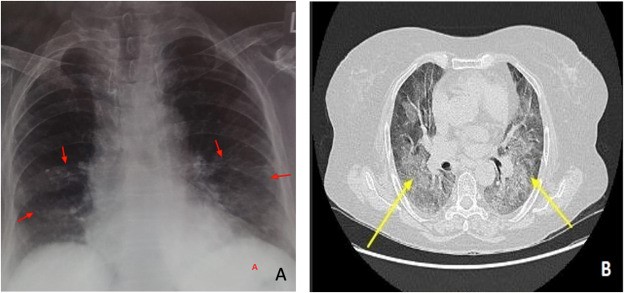

Фиброз н в

Фиброз н в 108 фото